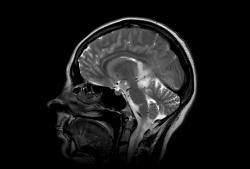

Женщина 47 лет, в течении долгого времени страдала от головных болей. В последние несколько месяцев - прогрессирующая потеря зрения (на оба глаза).

T2 ВИ Sagittal

Presented images are corresponded for cerebral (right temporal-occipital region) neoplasia; high grade glioma is most suggested.

Глиальная опухоль.